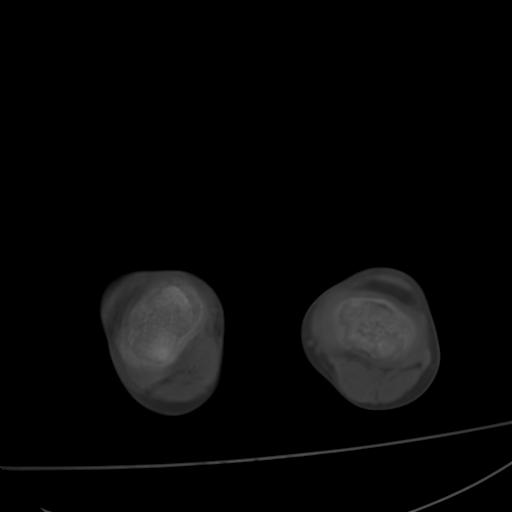

标题: PED0940:M12Y,左股骨下端酸痛畸形 [打印本页]

标题: PED0940:M12Y,左股骨下端酸痛畸形

12岁男孩,左膝关节肿痛8年,近月明显

内生骨软骨瘤?

血友性关节病?